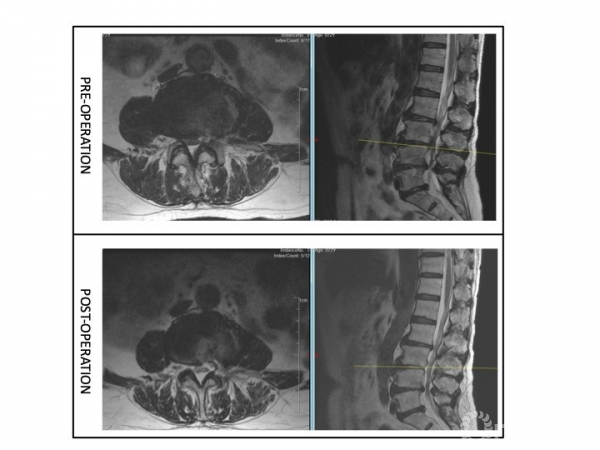

解决方案:根据主诉、查体、辅助检查,术前需要明确致痛节段。首先,予患者局麻下行腰椎间盘造影(L2/3,L3/4,L4/5)(图5),在L3/4节段注射造影剂约2ml时,诱发出患者下腰痛症状,继续注射造影剂增加盘内压力后复制出左下肢放射痛,考虑该节段椎管空间狭小,遂予L4/5节段左椎间孔行L4出口神经根选择性神经根封闭,后患者左下肢疼痛明显缓解。

图5

患者约2天后左下肢疼痛复现,遂于局麻下为患者实施了L3/4经皮内镜下腰椎间盘切除术,术中发现神经根与纤维环粘连,松解粘连,术后患者疼痛得到完全缓解。左侧直腿抬高试验与股神经牵拉试验转阴。术前后核磁可见该节段神经压迫解除。(图6)

图6

解决方案(图9):

① 腰椎间盘造影L3/4:注射2.5ml造影剂后,造影剂沿HIZ向椎管内渗漏,但未诱发下腰痛或放射痛;

② 腰椎间盘造影L4/5:注射2.5ml造影剂后,造影剂在间盘内分层,诱发出下腰痛,复制出轻度的左下肢放射痛;

③ L5出口根造影:穿刺针刺激出口根,复制出明显相同部位的放射痛,局部注射造影剂0.5ml[2],沿出口根走行显影,局部注射局麻药+类固醇封闭,患者疼痛缓解。下床行走约200m后,未出现间歇性跛行症状。患者要求暂保守治疗出院。

④ 因患者应用局麻及类固醇止痛、缓解炎症,验证性试验同时,具有治疗作用,如患者症状复现,可择期行L4/5节段内镜下单侧入路双侧减压术或单节段MIS-TLIF进行椎管减压。

图9